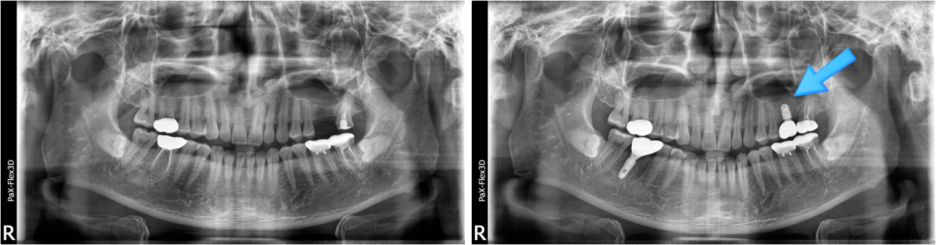

잇몸뼈 부족으로 상악동거상술을 통한 뼈이식 진행한 환자분의 x-ray

이를 상악동거상술이라고 하는데요. 이 상악동거상술을 동반한 뼈이식이 진행된다면 비용은 50~100만원 정도가 됩니다.